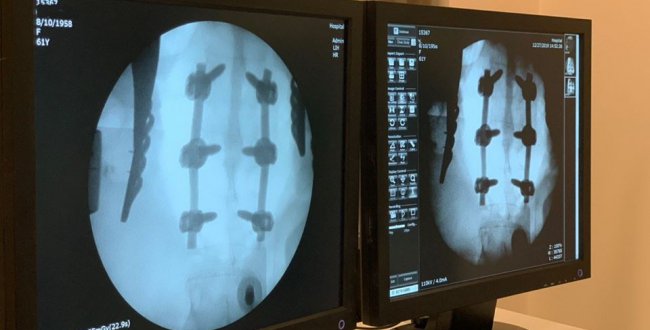

Лікарі врятували волинянку, яка впала з висоти і травмувала хребет (ФОТО 18+)

На Волині ковельські лікарі прооперували жінку, яка впала з висоти та сильно травмувала хребет. Про це повідомили на сторінці Ковельського МТМО у Facebook. Як повідомляють лікарі, […]